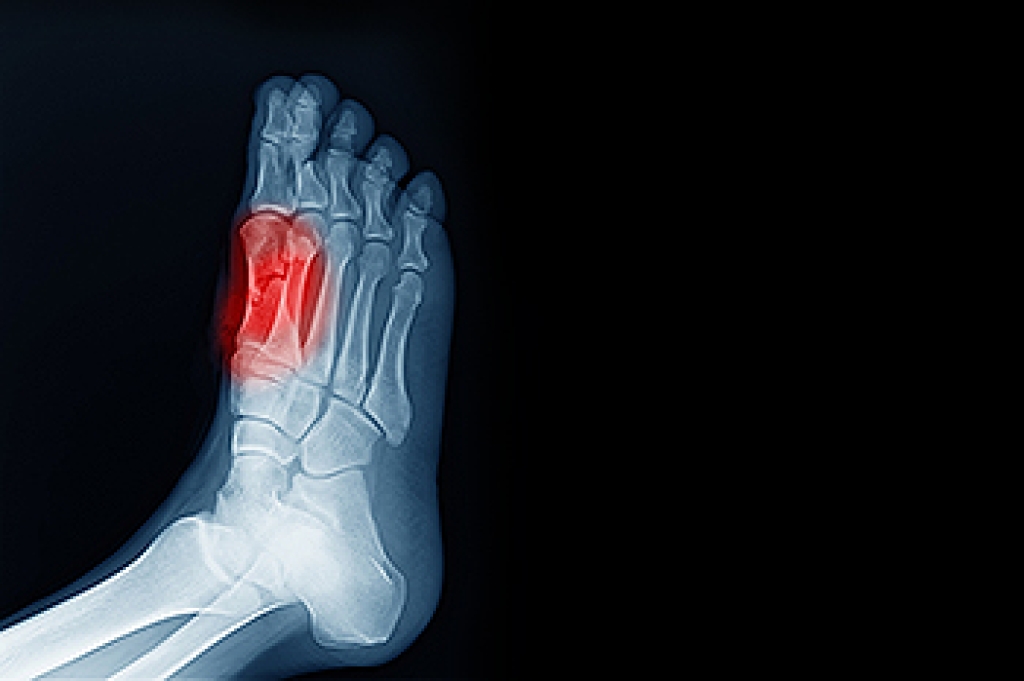

As people age, their feet often undergo changes that can affect comfort and mobility. Common foot issues among seniors issues include arthritis, which causes joint stiffness and pain, diabetes, which increases the risk of infections and poor healing, in addition to foot deformities such as corns and bunions that can make walking uncomfortable. These changes may develop gradually but can significantly impact daily activities and overall health. A podiatrist can assess foot health, provide treatments to relieve pain, and recommend proper footwear to improve stability and function. Routine foot care can help prevent complications and maintain independence. If you or a loved one are experiencing foot discomfort, it is suggested that you visit a podiatrist who can treat various foot conditions, while helping you to maintain your overall foot health.

When people age, some common issues that may occur are bone density loss, dry skin, poor circulation, and rough brittle nails. These issues may also affect your foot health if the necessary steps are not taken to alleviate the problems.

It is important to take care of your feet because feet that are injured or diseased can affect your overall health. Having painful feet hinders your ability to do daily activities or may decrease your willingness to do the things that you need to do.